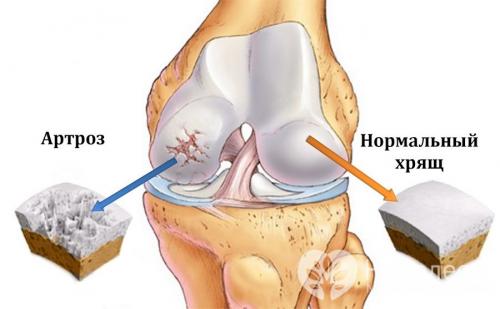

Механизм развития артроза

Развитие артроза начинается с разрушения хряща. В результате появляется боль и хруст при движениях . Ширина суставной щели постепенно уменьшается, по краям суставных поверхностей образуются костные шипы-остеофиты .

В конечном итоге сустав деформируется, амплитуда движений в нем уменьшается. Так развивается инволютивный артроз, связанный со старением организма. Развитие этой формы артроза обычно происходит постепенно, в течение многих лет.

Разрушение хряща при артрозе коленного сустава

Коленный сустав образуется суставными поверхностями бедренной и большеберцовой кости. Передняя поверхность коленного сустава защищена надколенником (коленной чашечкой). Суставные поверхности бедренной и большеберцовой кости, как и задняя поверхность надколенника, покрыты плотноэластичным гиалиновым хрящом, толщина которого составляет 5-6 мм. При ударных нагрузках хрящ выполняет амортизирующую функцию, а при движениях уменьшает трение. У клинически здоровых людей процессы синтеза и разрушения хрящевой ткани находятся в равновесии, когда равновесие нарушается в сторону увеличения деструкции, развивается артроз. При артрозе коленного сустава в мелких внутрикостных кровеносных сосудах, питающих гиалиновый хрящ, нарушается кровообращение, вследствие чего поверхность хряща становится более сухой, а со временем утрачивает гладкость. На поверхности гиалинового хряща образуются трещины, что служит причиной регулярного микротравмирования хряща при движении. С прогрессированием патологического процесса хрящевая ткань истончается, суставная площадка расплющивается, адаптируясь к нагрузке. По краям суставных поверхностей возникают остеофиты, которые представляют собой костные выросты, формирующиеся по причине компенсаторного разрастания костной ткани. Патологический процесс захватывает синовиальную оболочку и капсулу сустава. Суставная жидкость становится более вязкой, хуже выполняет свои функции, что приводит к усилению деструктивных процессов в суставе. При дальнейшем прогрессировании заболевания хрящ истончается еще больше, на некоторых участках исчезает вовсе. Это приводит к резкому усилению трения между суставными поверхностями и деформации костей, образующих сустав. Коленный сустав деформируется, деформация может быть вальгусной, т. е. Х-образной, или варусной, т. е. О-образной. Движение в пораженном суставе ограничивается вплоть до полного исчезновения (формируется– необратимое и полное разрушение сустава).